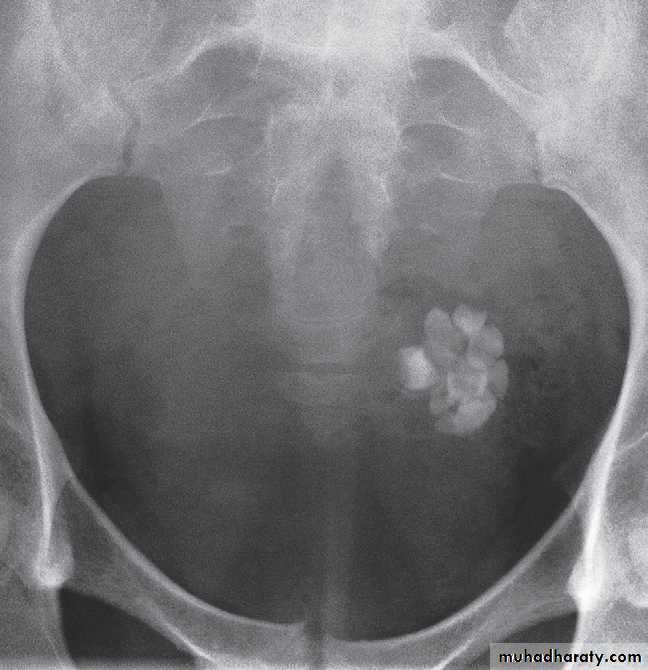

FibroidsLeiomyomas (fibroids) are common in women over 30 years of age. They are often asymptomatic, but may cause menorrhagia or present as a palpable mass. When sufficiently large, a fibroid can be seen on a plain film as amass in the pelvis and may show multiple irregular but well-defined calcifications .